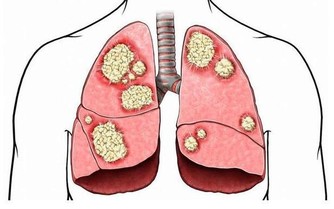

咳嗽

是呼吸系統中最常見的症狀之一,是人體的一種保護性措施,對機體是有益的。當呼吸道黏膜受到異物、 炎症、分泌物或過敏性因素等刺激時,即反射性地引起咳嗽,有助於消除自外界侵入呼吸道的異物或分泌物、消除呼吸道刺激因子。如果一咳嗽就用止咳藥物,則把加重炎症的髒東西都滯留在呼吸道裡不利於炎症的消除。

出現咳嗽時,應在保暖的同時補充大量水分,同時避免胡椒、洋蔥等辛辣食物刺激呼吸道。如頻繁咳嗽還伴有發燒、胸痛、體重減輕等症狀時,應立即就醫。